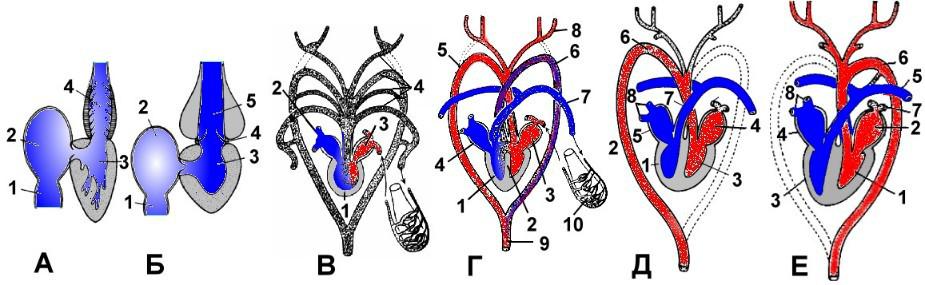

Особенности и диагностика левостороннего кровотока